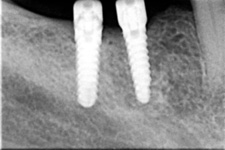

V případě chybění většího počtu zubů v postranních úsecích čelistí je možné ošetření pomocí implantátů, které nahradí ošetření pomocí snímacích náhrad kotvených na zbývajících zubech nebo patře.

Podmínkou je opět dostatečné množství kosti.

Protetické řešení může být pomocí můstku, který je kotvený na implantátech nebo pomocí jednotlivých korunek na implantátech.